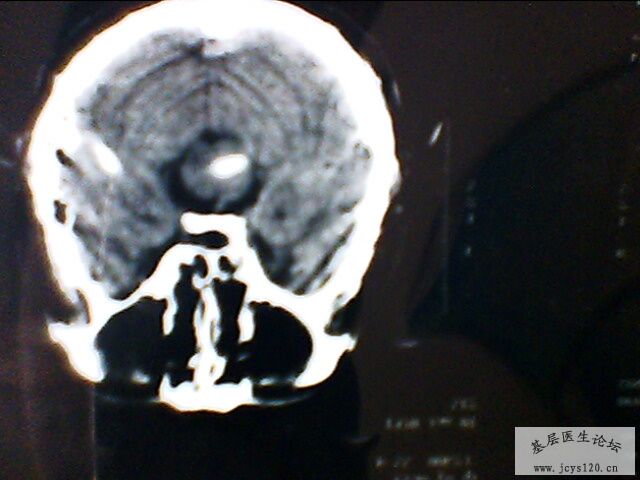

辅助检查:急诊颅脑CT:桥脑处见一卵圆形高密度灶,最大直径1.0cm,右基底节处见多个不足1.0cm大小的低密度灶,侧脑室前后角分布均匀的低密度灶,脑室及脑沟裂未见异常,中线结构居中。 CT意见:脑血肿 皮质下动脉硬化性脑病

从患者CT上大家应该可以看出,建议大家对比一下患者发病时的CT片子,桥脑部位的出血(高密度)现在密度降低,上级医院CT诊断为出血吸收期,所以患者目前正在恢复当中!!!!